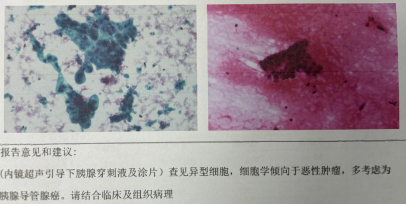

在充分的术前准备和家属沟通后,手术如期进行。精准诊断阶段:消化内科温蕾医生首先进行EUS检查。内镜前端的高频超声探头紧贴消化道壁,对胰头部病灶进行了360度无死角扫描,清晰地显示了肿瘤的大小、边界及其与周围血管的毗邻关系。在实时超声的精确引导下,穿刺针犹如“GPS导航”般,毫厘不差地穿越十二指肠壁,直达肿瘤核心,成功获取了足量的条索状组织,为病理诊断奠定了坚实基础。紧急治疗阶段:随后,无缝切换至ERCP操作。蒋承志医生熟练地把十二指肠镜抵达十二指肠乳头,造影清晰显示肝外胆管重度狭窄。导丝顺利通过狭窄段,一枚覆膜金属支架被精准释放于梗阻部位。瞬间,淤积的胆汁得以顺畅流入肠道,梗阻成功解除。整个手术过程流畅,患者无特殊不适。术后病理结合免疫组化,迅速明确诊断为胰腺导管腺癌。随着支架起效,患者黄疸快速消退,肝功能指标显著改善,为后续可能进行的抗肿瘤治疗赢得了宝贵时间和身体条件。